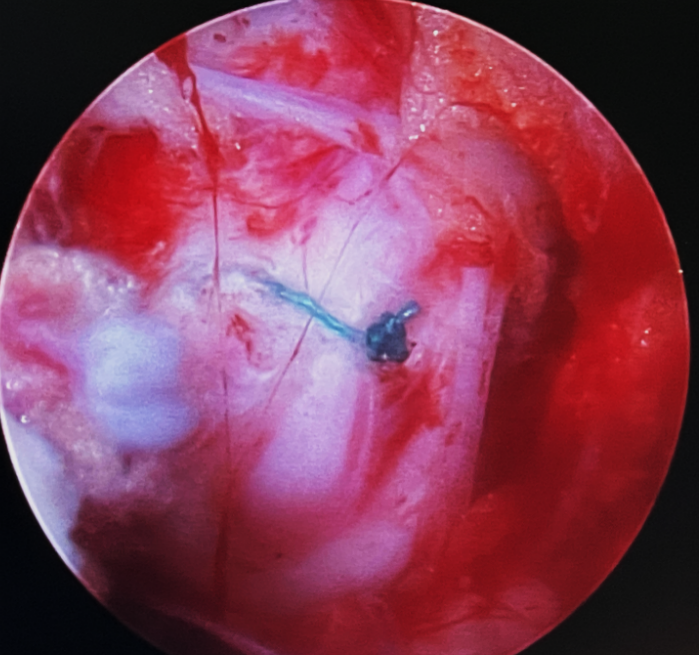

二、硬膜破裂(2.27%)

是常见并发症之一,发生率约2.9%。临床常见表现为头痛,包括直立性头痛、间歇性头痛、用力时头痛、眩晕、颈后疼痛、颈部僵硬、恶心、复视、畏光、耳鸣、视力模糊、脑脊液漏形成、假性脑膜膨出、脑膜炎、蛛网膜炎和硬膜外脓肿等。

常见原因:

学习曲线早期,经验不足

操作时出血较多易造成视野不清晰

硬脊膜与黄韧带粘连

过度追求完美增加不必要的手术操作

治疗:

硬膜破裂直径<4 mm:保守治疗

硬膜破裂直径 4-12mm:纤维蛋白补片

硬膜破裂直径>12mm:

边缘规则:内镜下修补(钛夹)

边缘不规则: 显微镜下硬膜修补

思考和建议:

术中精细操作,避免硬膜囊损伤

钙化的椎间盘及翻修手术谨慎应用UBE

损伤较小:紧密缝合

损伤较大:显微镜或通道下硬膜修补